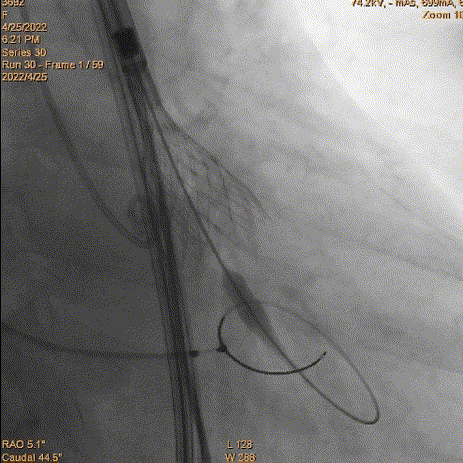

5、瓣膜定位和释放:参考猪尾中段1/3作为起始点。由于猪尾未到达窦底,参考1/2,参考Cusp overlap角度。造影确认位置,开始释放,1/4圈满满释放前1/3,起搏140bpm,压力逐步下降。

瓣膜定位评估

瓣膜释放

评估深度

评估深度-过深

6、瓣膜回收和再释放:到达2/3后小弯侧较深,经多角度评估评估较深,起搏回收再次释放。

瓣膜再次释放

7、释放完成:第二次释放评估深度合适,缓慢释放脱钩,同轴性良好。撤递送系统,撤抓捕器。

二次评估深度

缓慢脱钩